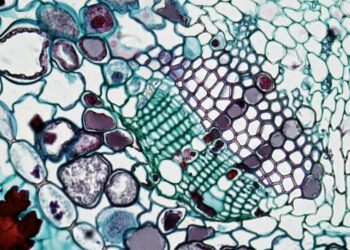

Read moreThe Gut Has Become a Theory of Everything

The intestine has been promoted from an organ system to an explanatory universe. Search and social discourse over the past...